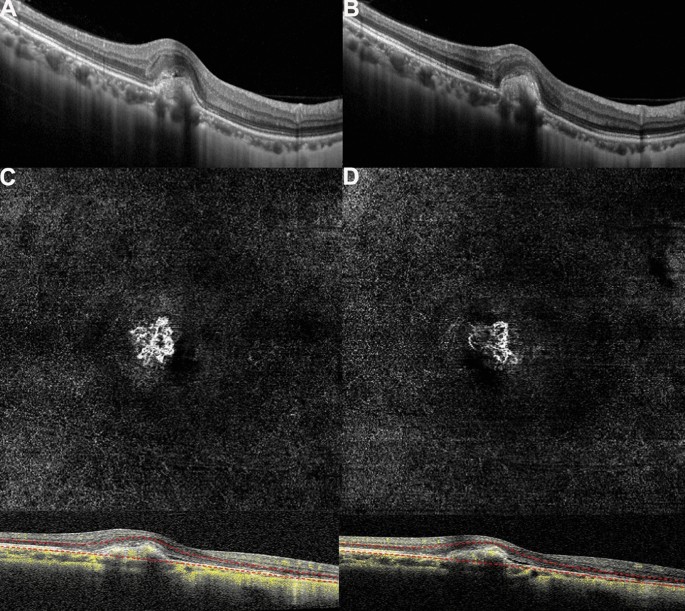

Before treatment, the morphological shape of the MNV in OCTA images was like a flower, fan, or small tree bud. Two subtypes of myopic MNV were distinguished10,11 on the basis of different characteristics in size and morphology: the well-organized larger “interlacing” pattern and the small, disorganized MNV “vascular loop” subtype (Figs. 3, 4). The intraobserver agreement was 95.2%. After conbercept injection, the small-diameter blood vessels of the MNV decreased, the intertwined small blood vessels decreased or even disappeared, and the main or larger-diameter blood vessels were still present, but blood flow was significantly reduced. The OCT and OCTA changes in a patient is shown in Figs. 3 and 4. The mean selected MNV area and blood flow area were 0.62 ± 0.81 and 0.22 ± 0.27 mm2, respectively, before treatment, and decresed to 0.23 ± 0.33 and 0.07 ± 0.08 mm2 (P = 0.04 for both), respectively, 1 month after conbercept treatment (Table 2).

(A,B) Optical coherence tomography (OCT) images of a patient with myopic macular neovascularization (mMNV) before and after receiving conbercept. Central macular thickness (CMT) decreased from 281.63 to 261.22 μm, and the hyperreflective signal lesions in the outer layer of the retina decreased. (C,D) Optical coherence tomography angiography (OCTA) images of the patient. MNV in both figures shows a small, vascular chaotic high-flow vascular network with a tree bud shape. The MNV areas in (C) and (D) are 0.54 and 0.23 mm2, while the blood vessel areas are 0.23 and 0.13 mm2, respectively.

The results of our study revealed that the average baseline vascular area of mMNV measured by OCTA was 0.62 ± 0.81 mm2, and the blood flow area was 0.22 ± 0.27 mm2. The vascular area of mMNV of our study is close to the finding by Miyata et al. (0.59 ± 0.56 mm2)23, which is significantly larger than the finding by Bruyere et al. (0.22 ± 0.27 mm2)10. Furthermore, we have distinguished two subtypes of mMNV similar to those of Bruyere et al., with different characteristics of size and morphology: a large, highly organized, interlacing high-flow network containing small capillary ramifications, bordered by a dark halo, with feeder vessel (Fig. 3) and a small, disorganized MNV “vascular loop” subtype, showing irregular blood flow and a small tree bud-shaped lesion composed of a small number of discontinuous linear branch blood flows(Fig. 4)10.

Previous studies reported the vacular remodeling of MNV after anti-VEGF therapy in nAMD on OCTA24,25. In nAMD, the pruning of smaller vessels occurred 24 h after anti-VEGF treatment, increasing and reaching the maximum flow regression between 6 and 12 days, followed by reproliferation (reopening or new sprouting of the vessels) after 20–50 days24. In another case series, the authors identified two types of MNV morphology progression in after anti-VEGF treatment: constant patterns, conserving their disorganized morphology with tiny capillaries and loops, are suggestive for immature MNV; however, changing patterns are subject to arteriolization with thicker dilated vascular trunks and the absence of tiny ramifications, ultimately suggestive for a mature neovascular lesion25. In patients with mMNV, a study analyzed the 1-month follow-up course after anti-VEGF treatment. mMNV were classified as irregular mass, referred to as tree-in-bud or a nearly round-shaped mass with a continuous ring around the lesion. At 1 month, changes were observed with decreased MNV size, narrowed lesion with the pruning of thinner peripheral blood flow, and decreased network density6. Similarly, in our study, the mean blood vessel area was 0.23 ± 0.33 mm2 and the mean blood flow area was 0.07 ± 0.08 mm2; both values significantly reduced compared with those of baseline (P = 0.04 for both) 1 month after intravitreal conbercept injection. OCTA images revealed that the capillaries and small-caliber feeder vessels were attenuated significantly after 1 month of conbercept treatment, which may have decreased the flow signals or caused these vessels to regress. However, the main central trunk vessel and large-caliber feeder vessels remained unchanged. These findings are similar to those of the study by Huang et al.26. Further studies are required to investigate the morphological changes in mMNV on OCTA, before and after treatment with anti-VEGF agents and the correlations between these changes and signs of neovascular activity.